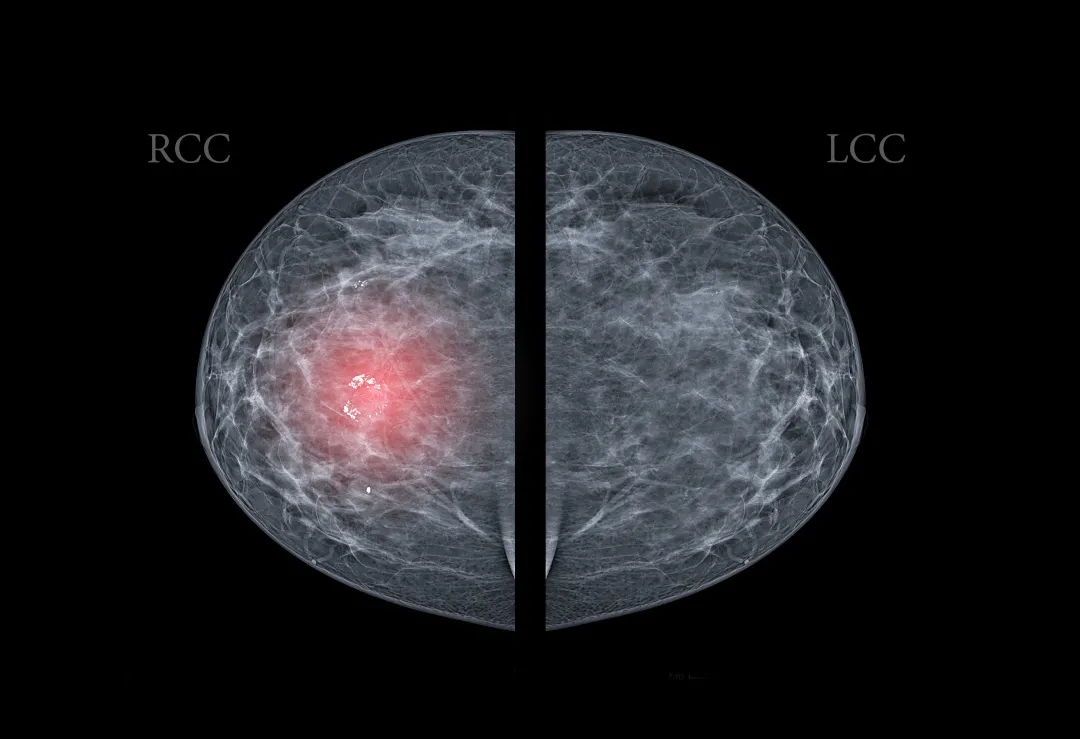

如何評判乳腺結(jié)節(jié)的惡變概率呢?其實我們可以通過一項報告來觀察乳腺結(jié)節(jié)惡變的風險等級:BI-RADS[3]。

BI-RADS是評價乳腺結(jié)節(jié)良性、惡性的統(tǒng)一分級標準,分為5個等級,用0~5進行表示,級數(shù)越高,惡性程度越高。

當診斷結(jié)果在BI-RADS-4類以上,考慮有較高的惡變幾率,應盡快前往乳腺外科就診,請醫(yī)生進行詳細評估。